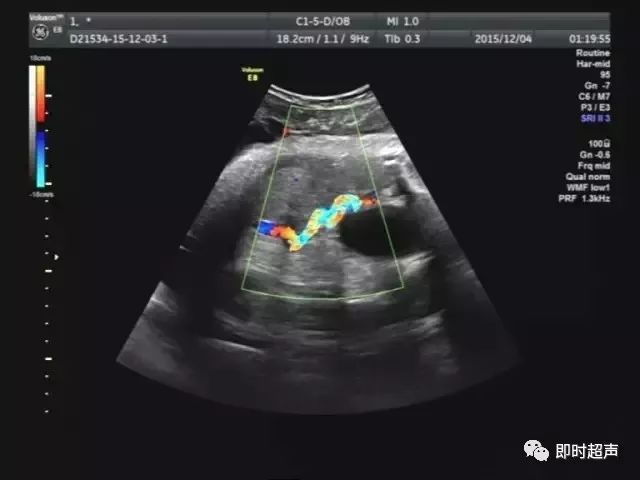

胎儿单脐动脉.

单脐动脉